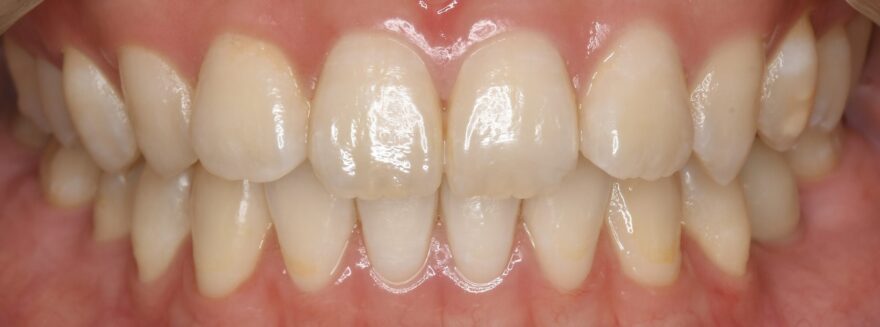

治療後の口腔内写真

約2年の治療期間で、ここまで美しい歯並びになりました。

前歯も綺麗に並びました。

インプラントの上部構造は仮歯からセラミック歯へと交換しています。

下顎の前歯にはワイヤーによる保定装置を装着しました。